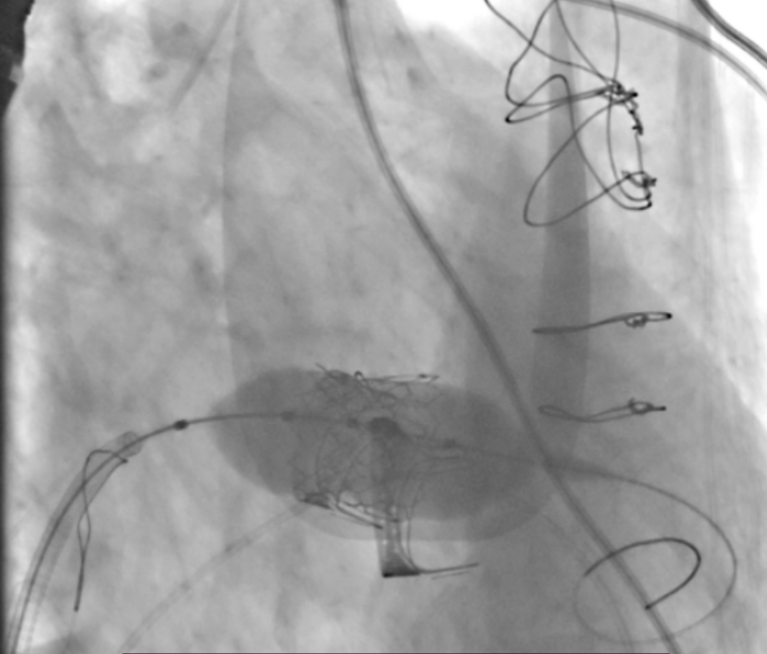

患者全麻后,穿刺右股静脉建立通路,穿刺房间隔,选用18mm球囊对房间隔进行扩张。泥鳅导丝跨二尖瓣后,根据术前评估情况,在180次/分快速心室起搏下,收缩压降至50mmHg,选用26mm Prizvalve®球扩瓣进行植入。瓣膜定位精准,释放顺利,撤出输送系统。随后,在圈套器的辅助下,导丝跨过三尖瓣,根据术前评估情况,选用29mm Prizvalve®球扩瓣进行植入。手术顺利完成。

三尖瓣球扩瓣释放